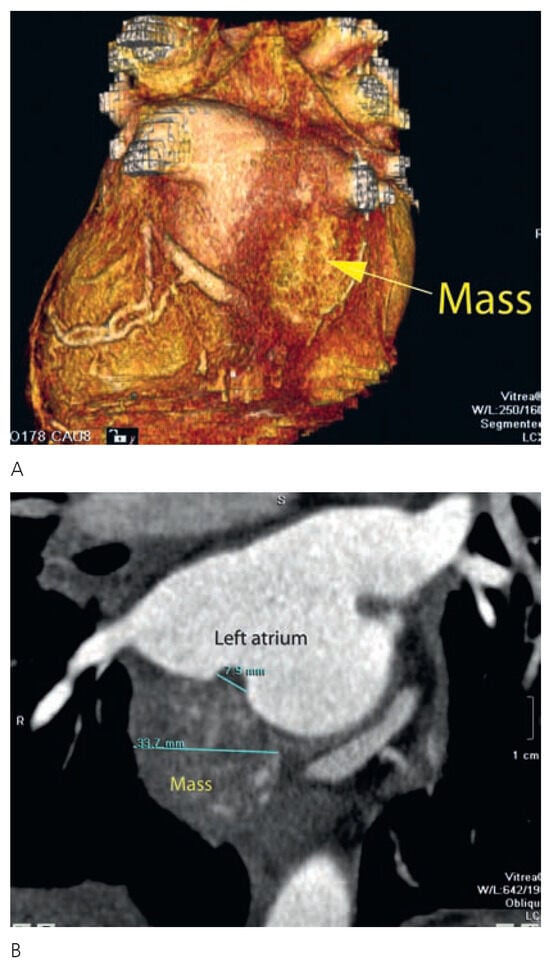

Clinical status showed: BP 150/65 mm Hg. Pulse regular at 82 beats per minute. Peripheral oedema was absent. Several peripheralsigns of aortic regurgitation were noted and a 3/6 protodiastolic murmur was present. Aortic valve replacement was decided and pre-intervention investigations were planed. Transthoracic echocardiography confirmed the aortic regurgitation grade III with mild dilatation of the left ventricle. Thoracic CT scan showed a 30 mm mass located within the left posterior wall (Figure 1). Transoesophageal echocardiography confirmed the location and dimensions of the tumour (Figure 2) and showed in addition involvement of the left atrial wall. Resection of the mass was performed during valve replacement (Figure 3). A 3 cm friable mass attached to the posterior wall of the atrium was easily removed. Reparation of the atrium was performed and a 23 mm aortic artificial valve was implanted. The outcome was uneventful. Histological and immunohistochemical examination conclude to a benign tumorous process compatible with the diagnosis of glomangiopericytoma (myopericytoma) (Figure 4). This was an unexpected diagnosis since to our knowledge it is the first case of cardiac benign haemangiopericytoma reported and secondly because of the patient’s history. A post irradiation tumour would have been more probable. Haemangiopericytoma is a rare tumour. The few one located in the heart were malignant.

Figure 1.

A 3D-CT scan showing the posterior mass attached to the left atrial wall. B 2D-CT scan. The mass is visible posteriorly infiltrating the atrial wall close to the pulmonary veins.